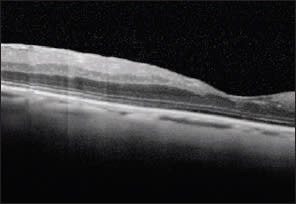

4. Epiretinal Membrane: OCT vs. Digital Fundus Photo

Most Optimal Technique

Advantages: Comparative measurements of progression; better analysis of complications with macular pucker and macular hole.

Limitations: Cannot see entire extent of surface over which puckering may occur.

Alternative Technique

Advantages: Can see surface area over which puckering may occur.

Limitations: Cannot quantify membrane thickness and presence of edema.